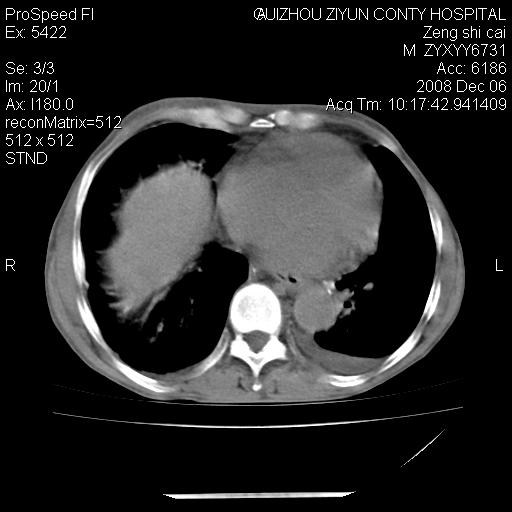

标题: CT16961:M、71岁,咳嗽半年,无血痰;胸片示右肺占位。 [打印本页]

标题: CT16961:M、71岁,咳嗽半年,无血痰;胸片示右肺占位。

1)考虑右肺上叶纵隔型肺癌伴纵隔淋巴结转移。2)心包积液,双侧胸腔积液。

升结肠癌伴腹膜后淋巴结转移

右肺癌并纵隔淋巴转移,腹膜后转移可能性大,两侧胸腔积液

右肺上叶纵隔型肺癌伴纵隔淋巴结转移。心包积液,双侧胸腔积液。

建议强化!主要鉴别是淋巴瘤与肺癌淋巴结转移。